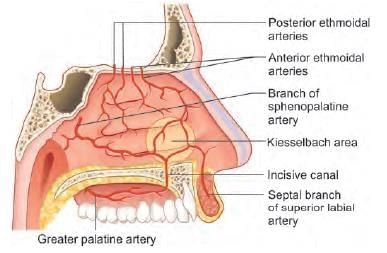

External carotid artery supplies nasal septum by all of the following branches, except: (AIIMS May 2019)